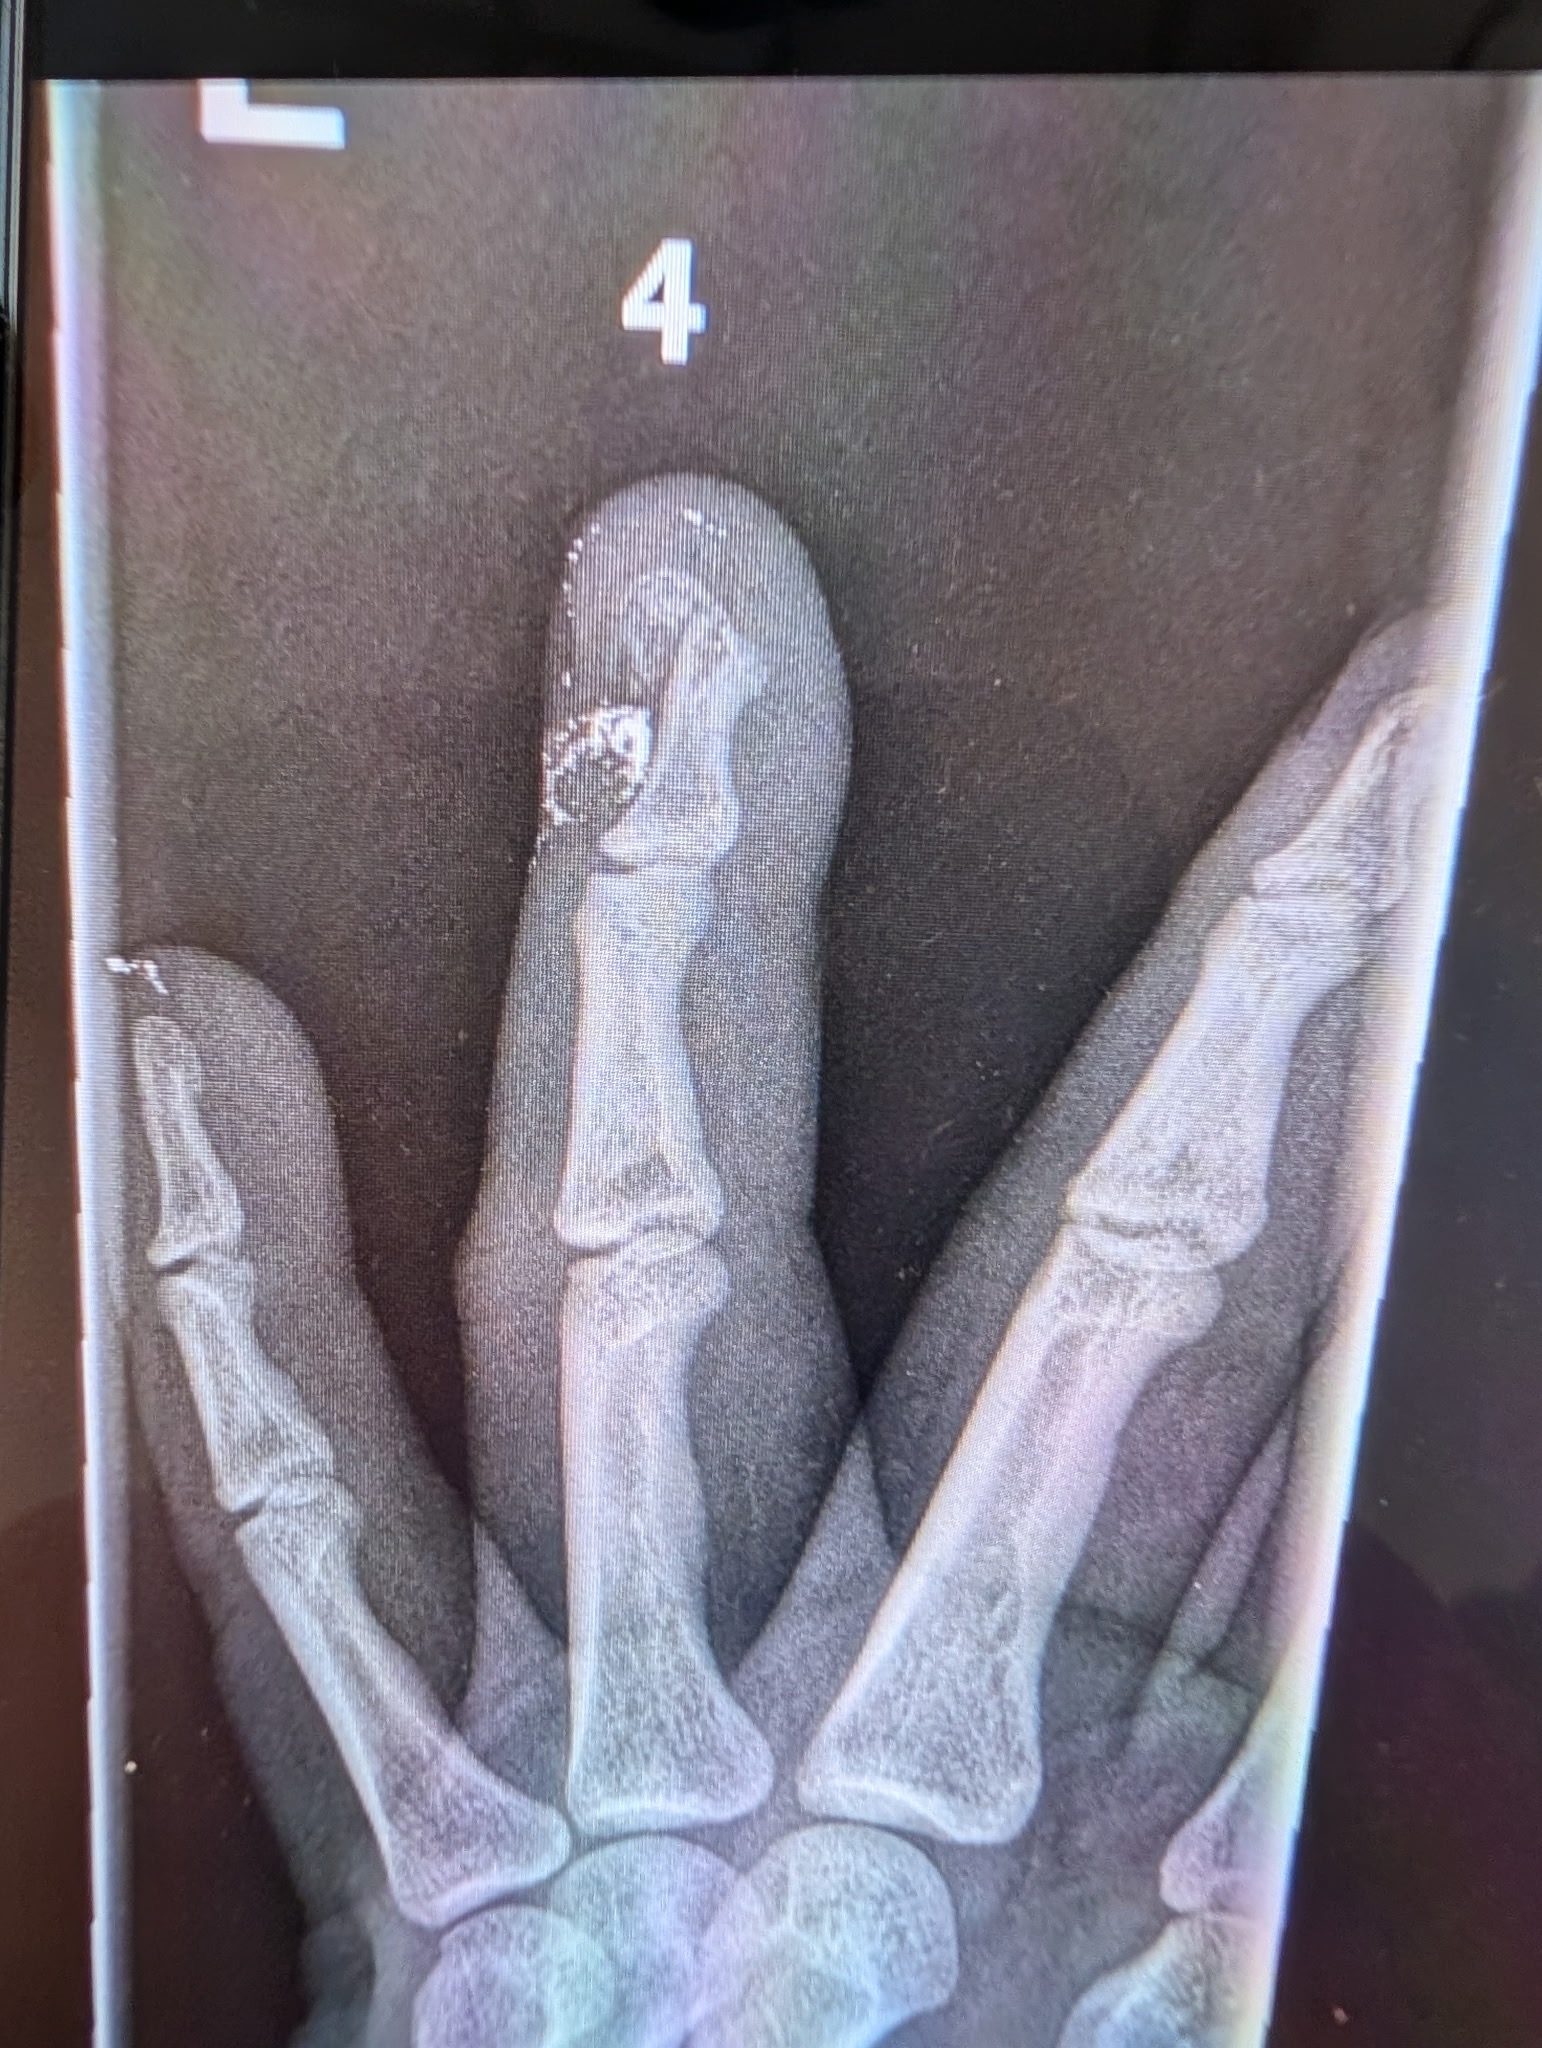

My name is Mario, and I am an independent media journalist dedicated to covering important events in our community. Recently, while reporting on a protest in front of the federal building in downtown Los Angeles, I was shot by a federal agent with a less lethal round. The impact broke my finger, and now I am facing surgery and a recovery period that will keep me out of work for an unspecified amount of time.